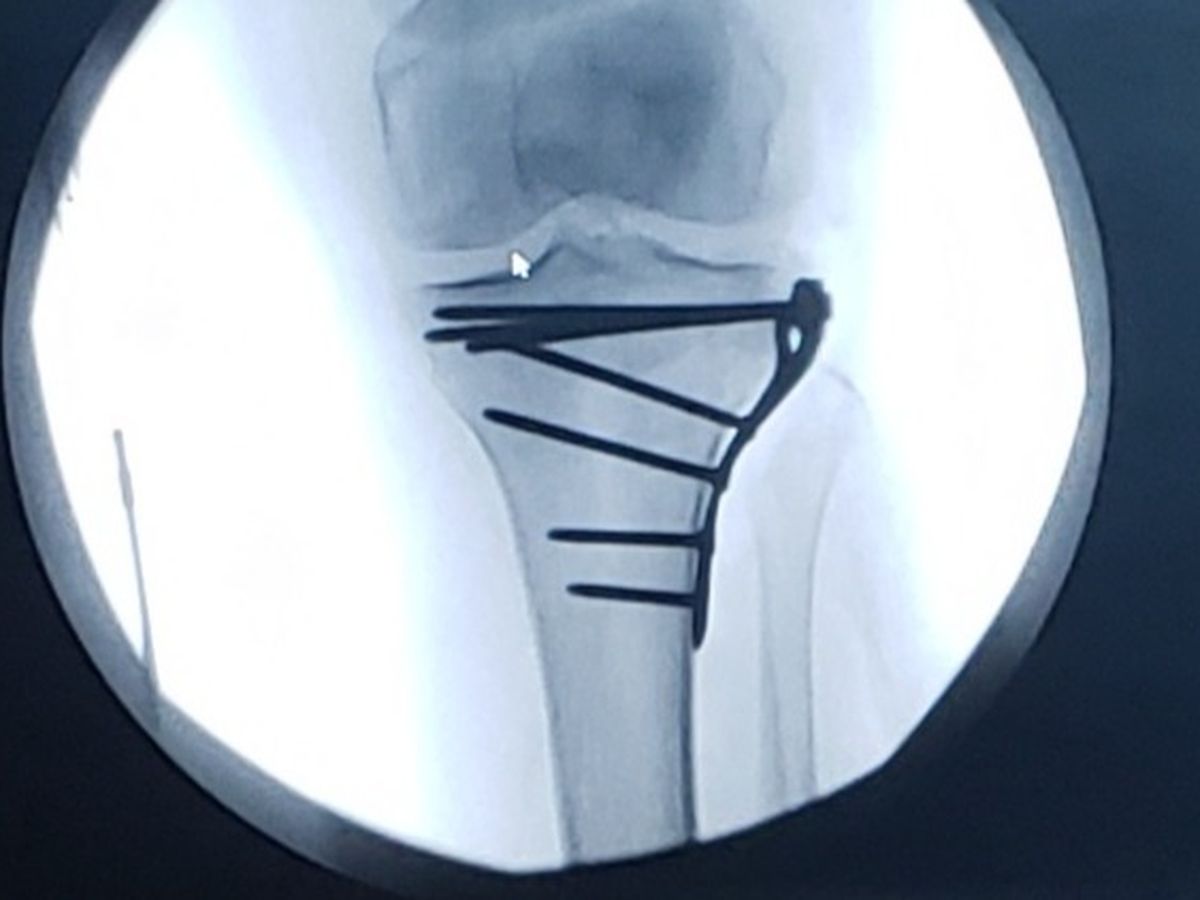

Hi! My name is Debbie Wilds. I am Dawn Dennison's Mother. As you may know, Dawn fell breaking both her legs below the knee. One leg had reconstructive surgery. Both legs are in braces. She will be non weight bearing for weeks. Please help me raise enough funds to cover her monthly expenses for this first month that she will be unable to work. Your generosity will be greatly appreciated.